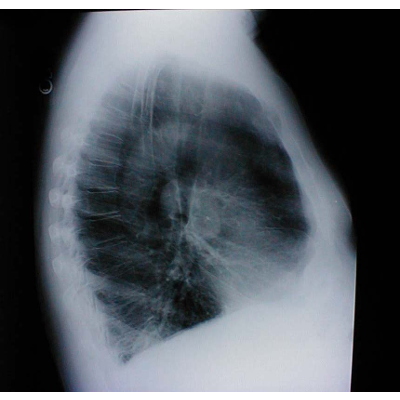

The Lung exam

Discusses the basics of lung auscultation and examinations. Includes abnornals, anatomy and physiology graphics, etc.